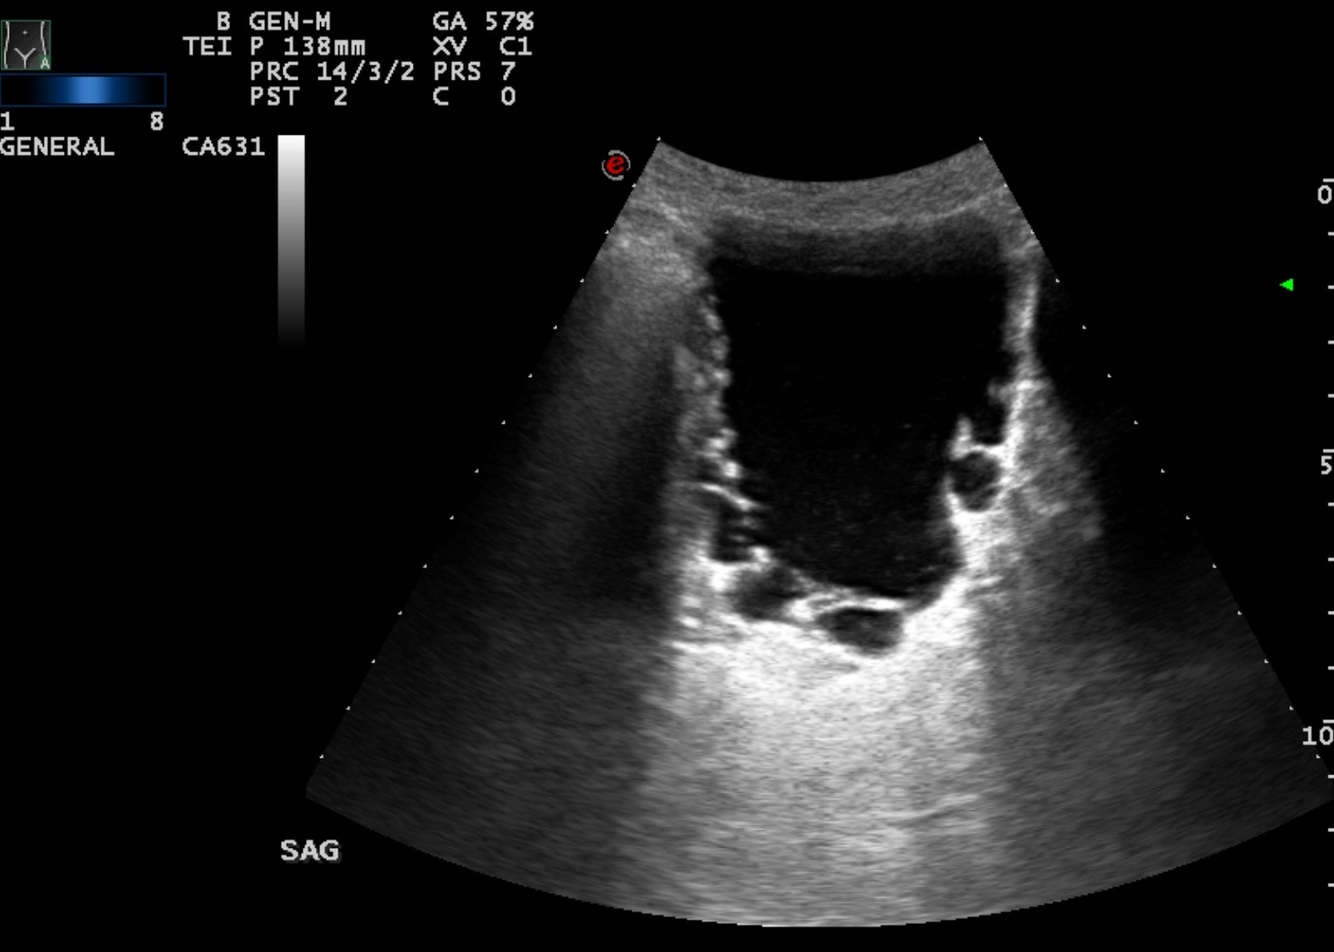

Acquired diverticulum in bladder outlet obstruction

Case courtesy of Dr Prat Matifoll, Radiopaedia.org, rID: 30578